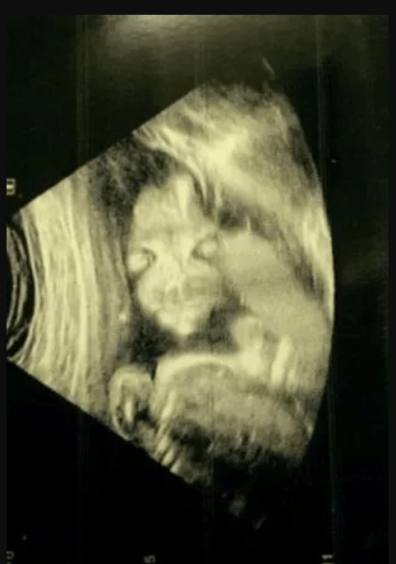

В Англії дівчина, на ім'я Джейд Бойленд поділилася своєю історією, як дала своїй дочці прізвисько "демонічна дитина". Річ у тому, що побачивши зображення свого майбутнього малюка на першому скринінгу, вона злякалася, оскільки жахлива постать була дуже схожа на зловісного персонажа з мультсеріалу "Зелені Обрубки" (Salad Fingers).

Про це пише Mirror. Джейд розповіла, що очікувала побачити класичний знімок бічного профілю дитини. Навіть сонографіст засміявся з дивного зображення, а потім швидко пояснив, що все виглядає нормально.

"Вона весь час дивилася назовні, ми не могли змусити її повернутися. Я намагалася змусити її рухатися. Не допомагало, вона не рухалася. Спочатку я злякалася, але потім мені стало смішно. Друзі та сім’я сміялися, коли побачили знімок. Я не думаю, що багато хто бачив щось подібне", — поділилася спогадами Бойленд.